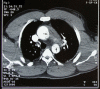

Acute aortic dissection can occur at the time of intense physical exertion in strength-trained athletes like weightlifters, bodybuilders, throwers, and wrestlers.Rapid rise in blood pressure and history of hypertension are the most common causes of aortic dissection in athletes. It is a very tragic event because of its high mortality rate of about 32% in young patients. We report a case of aortic dissection in a young weightlifter with an extensive intimal tear of the aorta, from the sinus of Valsalva to the abdominal aorta.